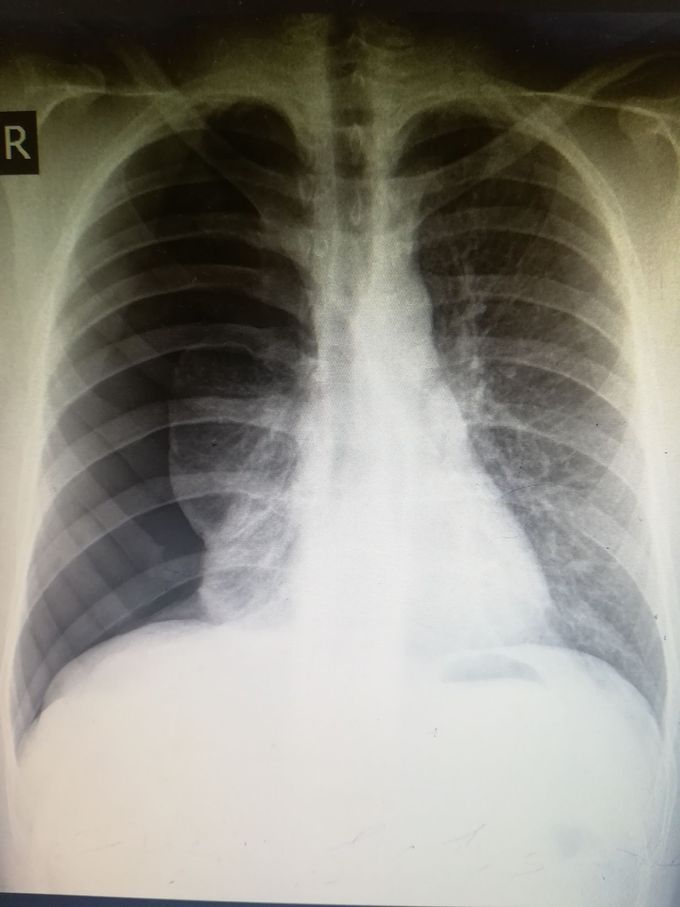

Sudden shortness of breath (chest xray) MEDizzy